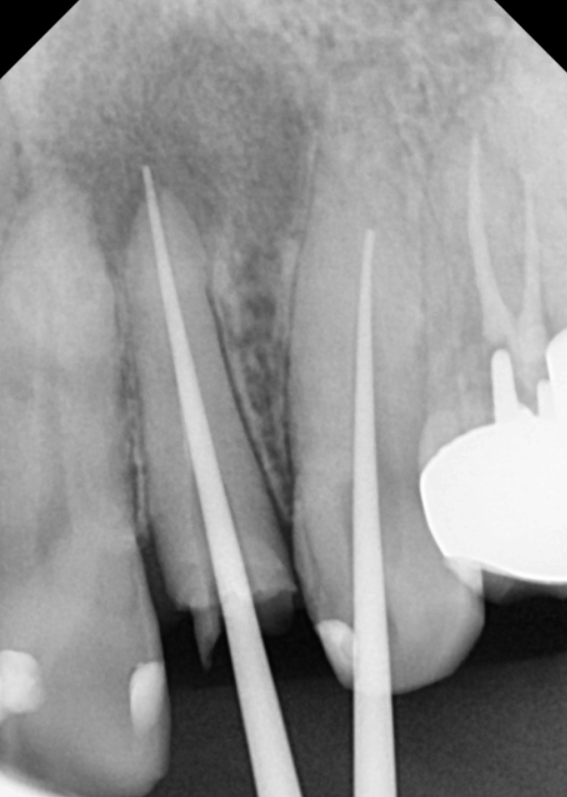

231207

오염된 부분을 완전히 비워내야만

새로운 길을 찾을 수 있으니까요.

이번 치료에서 가장 중요한 핵심이

무엇인지 아시나요?

바로 뿌리 끝까지 신경관의 길이를

완벽하게 찾아내는 것이에요.

신경관 길이를 끝까지 정확히 찾아내야만,

세균이 다시 번식할 틈을 주지 않고

이번처럼 염증 때문에 고생하시는 일을

확실히 방지할 수 있거든요.

신경치료 중 가장 기본적이면서도

중요한 과정이라고 할 수 있죠.

일반적으로 신경치료 소독은

2~3회 정도 진행하지만,,

이 환자분은 통증도 계속되고

염증이 워낙 컸기에

소독 과정을 총 10회에 걸쳐

아주 꼼꼼하게 진행했습니다.